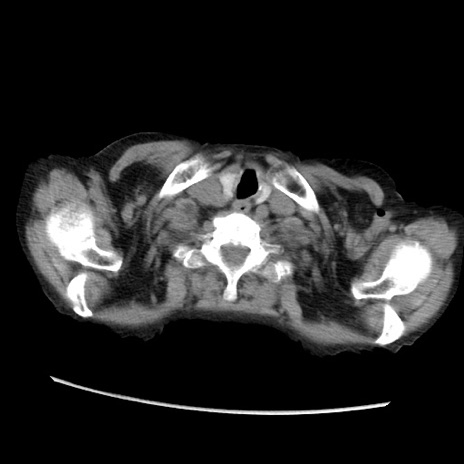

症例31(横断像)

【症例】80歳代 女性

【主訴】腹部膨満感

【現病歴】他院にて肝硬変にてフォロー中。1週間前から便秘、腹部膨満感、臍部腫瘤あり受診となる。

【既往歴】肝硬変

【身体所見】腹部膨隆あり、皮膚変化なし、疼痛なし。

【データ】WBC 4600、CRP 0.25